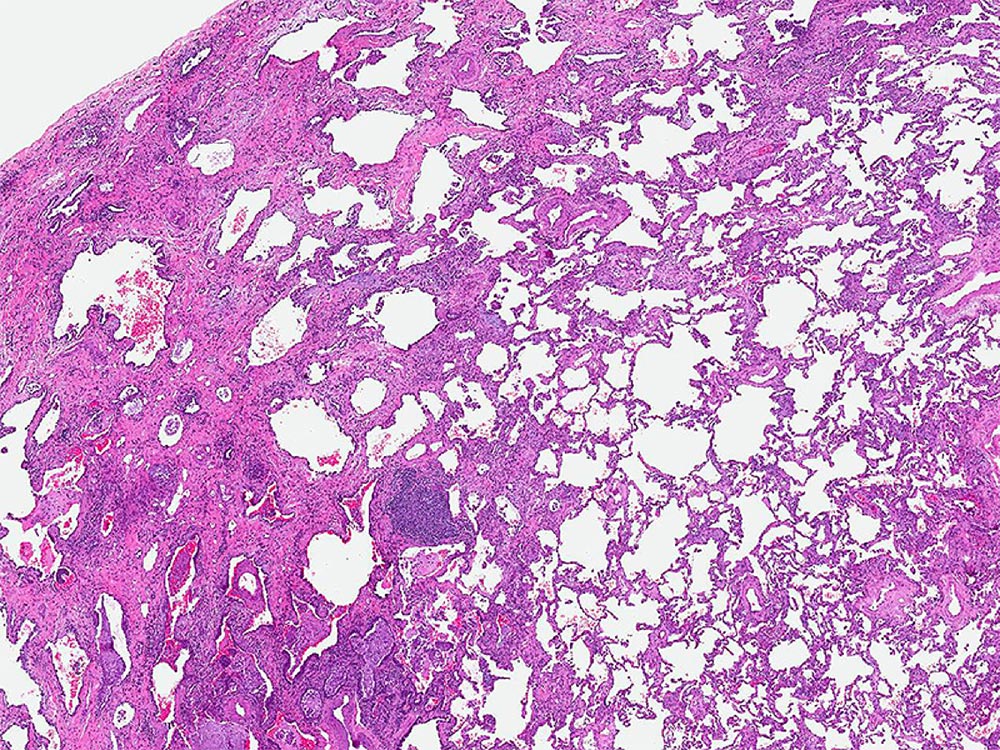

Low magnification photomicrograph showing subpleural fibrosis and honeycomb change. Unlike the heterogeneity of fibrosis seen with usual interstitial pneumonia (UIP), the process seen here is homogeneous throughout the lung and is and typical of fibrosing nonspecific interstitial pneumonia (NSIP).

Image courtesy of and used with permission from Kirk Jones, MD.